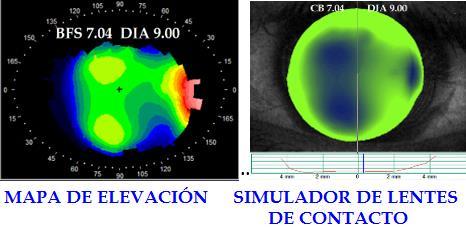

La contactología especializada ha logrado avances significativos en cuanto respecta a diseños y resultados correctivos con lentes de contacto, especialmente en casos de queratocono, ectasias postquirúrgicas refractivas y queratoplastias penetrantes, cuyas córneas adoptan formas únicas como huellas digitales, en las que, mediante tornos computarizados, se customizan dichos lentes con características exclusivas para el paciente que los porta. Aunque existen diferentes mapas de análisis topográfico corneal, los mapas de elevación representan la prueba más sensible para la detección temprana de ectasias como paradigma actual de la contactología, toda vez que los tomógrafos y equipos más sofisticados emplean dichos principios para generar sus reportes, yendo incluso hasta la predicción del comportamiento adaptativo de los lentes de contacto, mediante fluorogramas simulados antes de insertar el lente de contacto. En tal sentido, el artículo hace un abordaje de los principios e interpretación de la topografía por elevación, aportando elementos de análisis y aplicación clínica de los resultados, con enfoque práctico desde la contactología, como recurso indispensable para la adaptación ideal, especialmente en la casuística compleja anteriormente mencionada. Palabras clave: Topografía corneal, Mapa de elevación, Ectasia corneal, Astigmatismo.

ABSTRACT

Aunque esta técnica adopta variantes de mapas de registro topográfico con utilidades específicas para el estudio corneal, los mapas de elevación resultan más sensibles y aportan más información específica para la detección temprana de ectasias corneales; a diferencia de la topografía de curvatura, la de elevación obtiene su registro de curvatura mediante un sistema que integra la cámara de Scheimpflug (Figura 1) con incidencia en forma de hendidura,yunregistromedianteOCT(Tomografíade coherencia Óptica), que son generados simultáneamente por el dispositivo [6].

Algo similar ocurre con la topografía de curvatura, la cual ofrece poca información sobre la forma y solo proporciona datos de la superficie corneal,mientrasquelosdatosobtenidosmedianteel sistema de elevación, brindan información detallada de la forma real de la superficie corneal, independientementedeleje,orientaciónyposiciónde la zonaanalizada, ademásde la posibilidaddeobtener los mapas de curvatura anterior y posterior, elevación anterior y posterior, aberrometría y paquimetría corneal [8].

La elevación representada en el mapa indica la diferencia de altura en micras (µm) respecto a la BSF, representando en color verde el alineamiento exacto (0.0 µm), en colores cálidos la elevación por encima de la BFS con signo positivo, y en colores oscuros o fríos con signo negativo, las áreas ubicadas debajo de la BFS (Figura 4) [11].

ADAPTACIÓN DE LENTES DE CONTACTO ASISTIDA CON MAPA DE ELEVACIÓN

En la adaptación de lentes de contacto RGP corneales, el mapa de elevación representa una herramienta precisa que asemeja al patrón fluorográfico empleado en la adaptación tradicional

[14]; en principio, la BFS generada por el equipo equivale a la curva base de un RGP esférico situado sobre la córnea, que permite visualizar de modo preliminar el fluorograma estático (Figura 9), además de variar dicho valor referencial según cada caso, estrechando o aplanando la curva base del “lente

virtual” de prueba, para simular la adaptación real y reducir la cantidad de lentes de prueba empleados en la adaptación, lo que además de ahorrar tiempo en el gabinete, reduce la exposición mecánica e inconfort cornealderivadodepruebasdeadaptacióninsistentes con varios lentes de contacto.

DISCUSIÓN

Entre las numerosas aplicaciones de los mapas de elevación en la adaptación de lentes de contacto se destaca la interpretación del patrón original [7] (Figura 10), que junto a otras variables clínicas e idiosincráticas, permite elegir el tipo de lente de prueba inicial corneal o escleral , considerando quetoda alturas diferenciales de elevación inferiores a 350µmentrelospuntoscornealesmásaltoymásbajo permiten adaptaciones más exitosas, mientras que diferencias superiores sugieren el uso de lente de contacto esclerales [16].